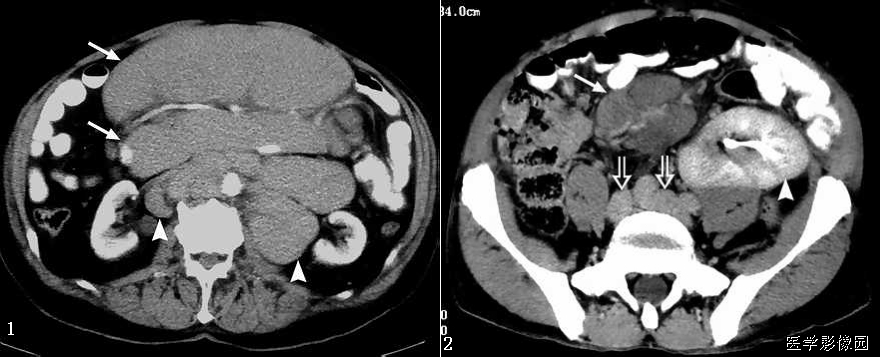

13、三明治征(夹心面包征或夹心饼征)

指2个均质软组织肿物组成三明治面包,系膜脂肪和管状物为构成夹心,是腹部CT横断扫描时的影像表现。系膜脂肪和血管组成夹心,肿大淋巴结组成面包;在给予增强剂后系膜管状结构(血管、肠管)相对脂肪增强,夹心层突出。因为淋巴结增大会压迫血管,阻碍静脉回流,使夹心层内增强的血管更加明显。

当经静脉及口服造影剂后,肠系膜血管结构较脂肪明显强化,从而可使夹心更加突出。导致肠系膜淋巴结肿大的病因很多。除淋巴瘤外,癌、肉瘤、类癌、获得性免疫缺陷相关性淋巴结增生综合征、结核、肠源性脂肪代谢碍及炎症性肠病等也是最常的病因。

三明治征为肠系膜淋巴瘤的特异征象。因为只有在肠系膜淋巴瘤中淋巴结才可以长得很大,并包绕脂肪、肠管和血管而不产生任何临床症状。肠系膜淋巴瘤偶尔可侵犯浆膜及固有肌层,有时会引起小肠出血但极少引起游离性穿孔。肠系膜淋巴瘤还可以引起腹膜后淋巴结肿大。

总之,三明治征指的是CT柏横断面上,巨大增生的肠系膜淋巴结包绕肠系膜脂肪和血管而形成的类似三明治的影像。对于设有移植病史的患者,非霍奇金淋巴瘤是三明治征的主要病因;有移植病史的患者,产生三明治征的原因则可能是淋巴组织增生性疾病,随着接受移植手术的患者不断增多,三明治征可能会在临床上越来越常见。

下图是一个恶性肿瘤腹膜后淋巴结转移患者:

下边两幅图更典型:

图1:非何杰金淋巴瘤患者口服造影剂后增强CT横断面。显示2个巨大系膜淋巴肿物(2个面包-带尾箭头),包绕中心系膜和增强的血管。注意增强的小肠位于周边,腹膜后淋巴结显著增生-箭头)。

图2:患者6个月前曾行左肾移植发现PTLD,血管和口服造影剂横断CT显示三明治征——系膜淋巴肿物(实心带尾箭头),靠近右肾(箭头),有腹膜淋巴结肿大(空心带尾箭头)。